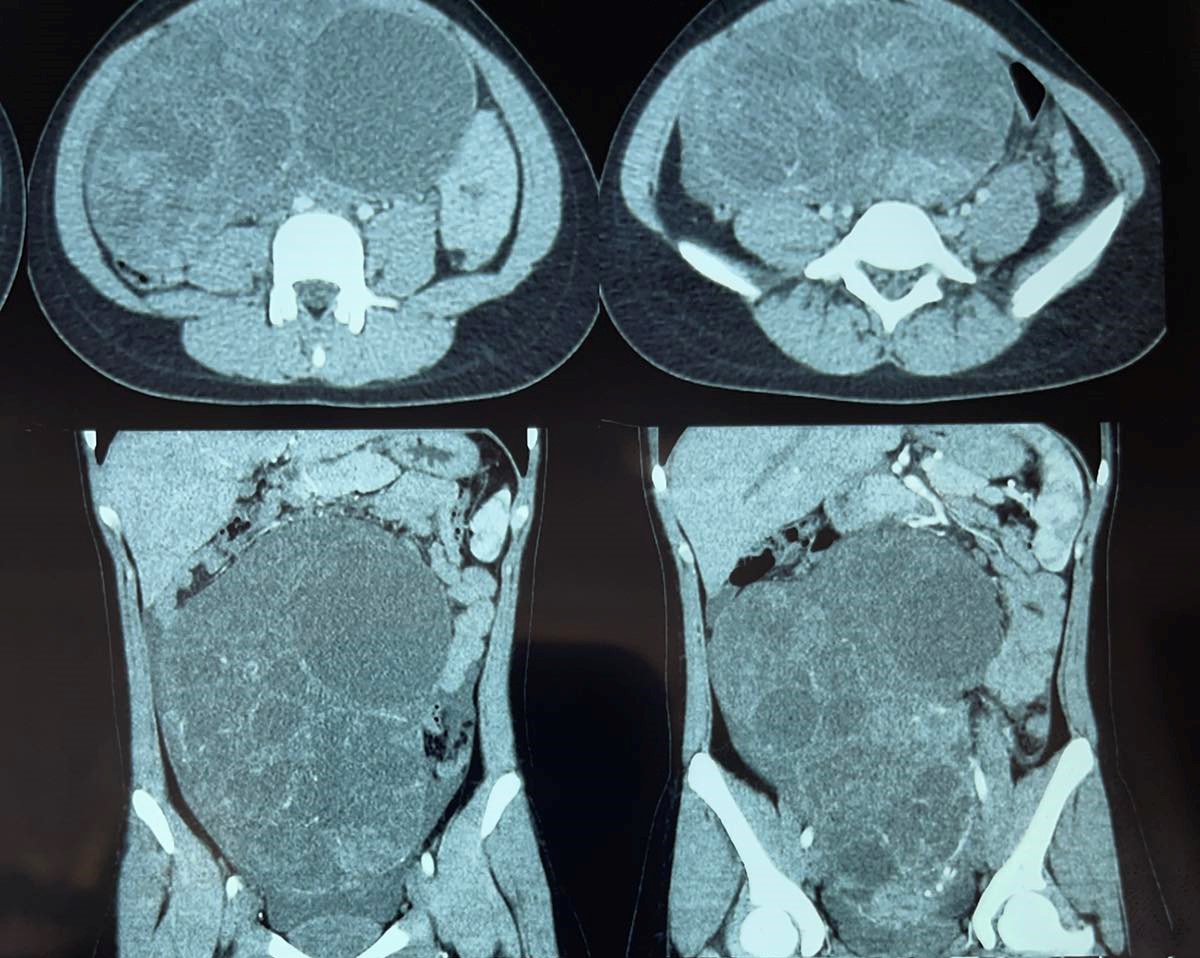

O adolescentă în vârstă de 15 ani cu tumoră ovariană cu celule granuloase de tip juvenil a fost operată cu succes de echipa de medicii chirurgi pediatri din cadrul Centrului Național științifico-practic chirurgie pediatrică „Natalia Gheorghiu”, Institutul Mamei și Copilului.

Potrivit IMC, tânăra pacientă a fost internată la spital acum 6 luni cu un istoric de 12 luni de dureri abdominale periodice, mărire a volumului abdominal și absența menstruației.

După efectuarea unor investigații imagistice, specialiștii au constatat prezența unei formațiuni chistice masive în abdomen, cu dimensiuni de 24,0 cm x 20,0 cm x 10,6 cm. Tumora care cântărea aproximativ 3 kg a exercitat presiune asupra organelor abdominale și pelvine, comprimând vezica urinară și provocând bombarea peretelui abdominal anterior.

După pregătirea preoperatorie corespunzătoare, medicii au

efectuat o laparotomie transrectală stângă, prin care au reușit să extirpeze

complet tumora care se dezvoltase în ovarul stâng al pacientei.